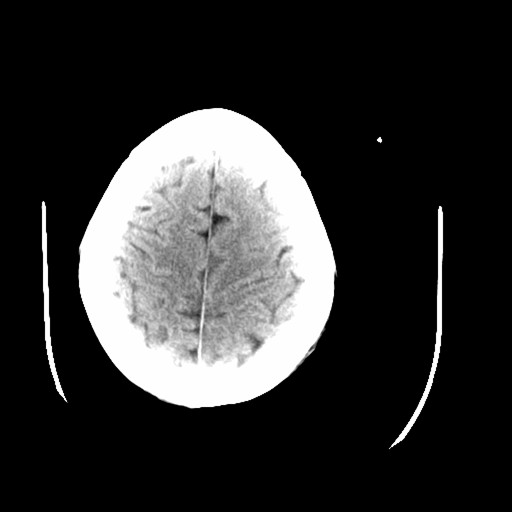

标题: CT16233:女,44岁,智障多年,现感头痛 [打印本页]

标题: CT16233:女,44岁,智障多年,现感头痛

老年脑,萎缩表现

脑萎缩

44岁  小脑表现为萎缩? 原因是什么呢?ct诊断上可报小脑萎缩吗?

脑萎缩表现

1)小脑萎缩。2)小脑蚓部发育不良。

小脑萎缩征,原因待定.